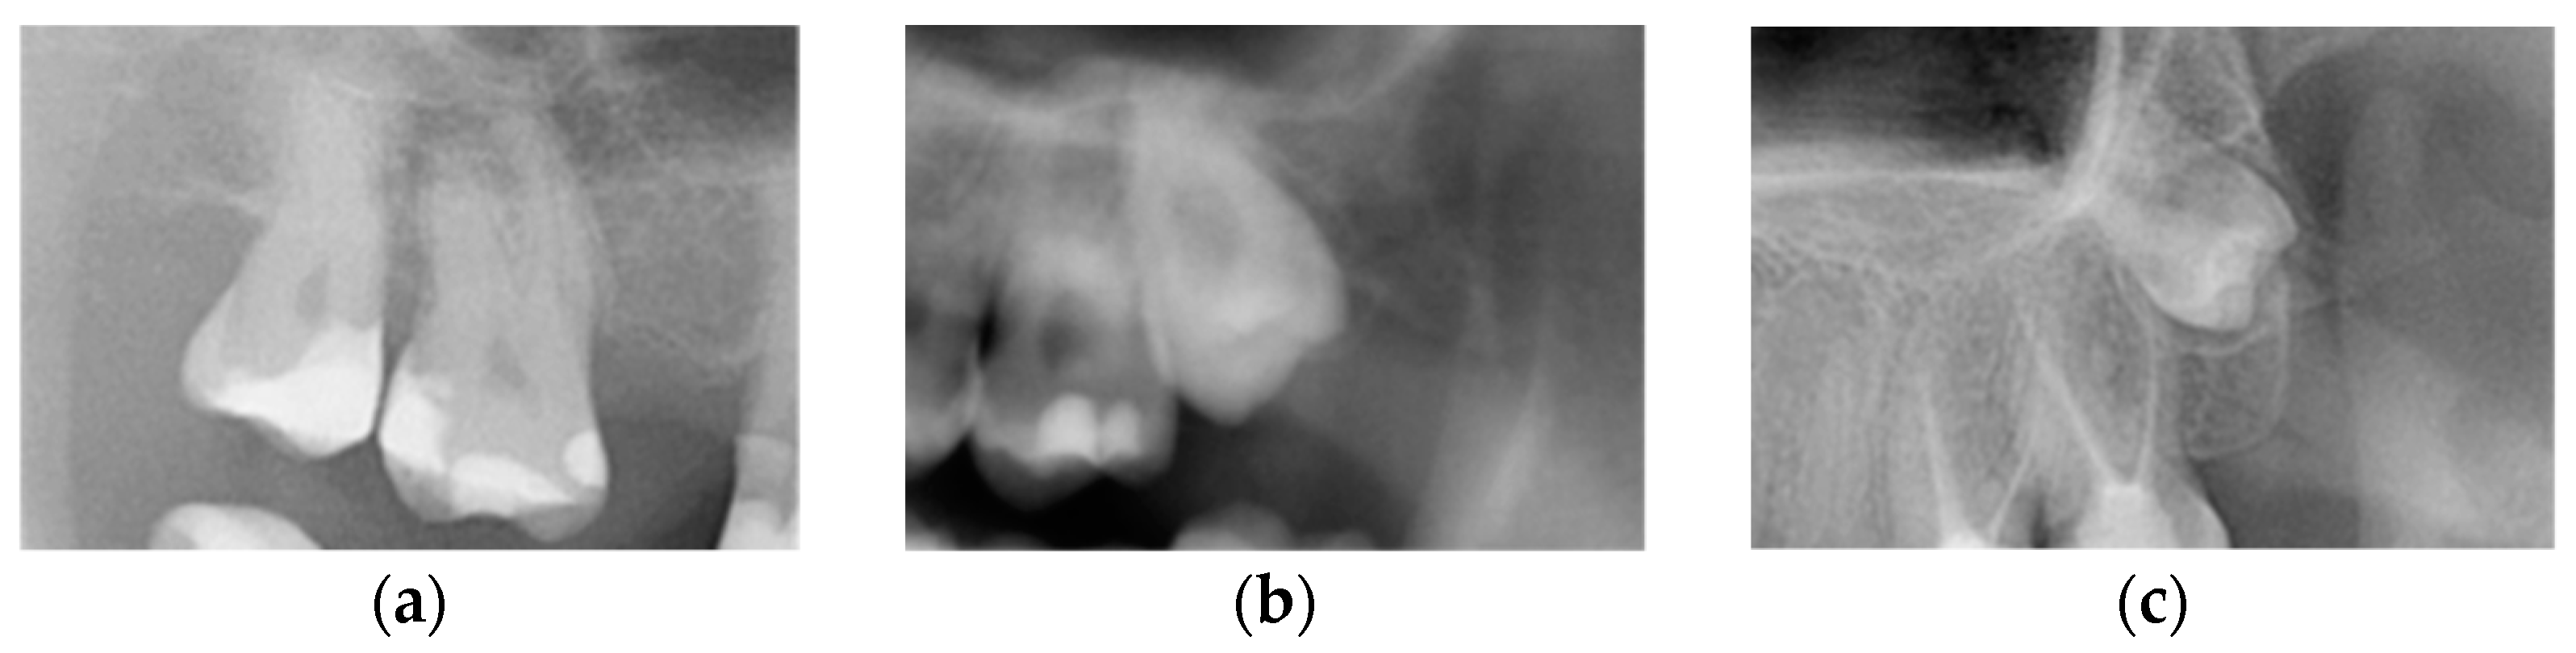

M3s were divided, according to the eruption status into (1) non-impacted (N-M3), when the tooth reached the occlusal plane, (2) completely impacted (I-M3), when the tooth was completely surrounded by bone, and (3) partially impacted M3, when the crown of a tooth was situated above the bone edge, but had not reached the occlusal plane (Figure 2) [2].

Figure 2. Third molars depending on the eruption status: (a) non-impacted (erupted) M3, (b) partially impacted M3, and (c) completely impacted M3.